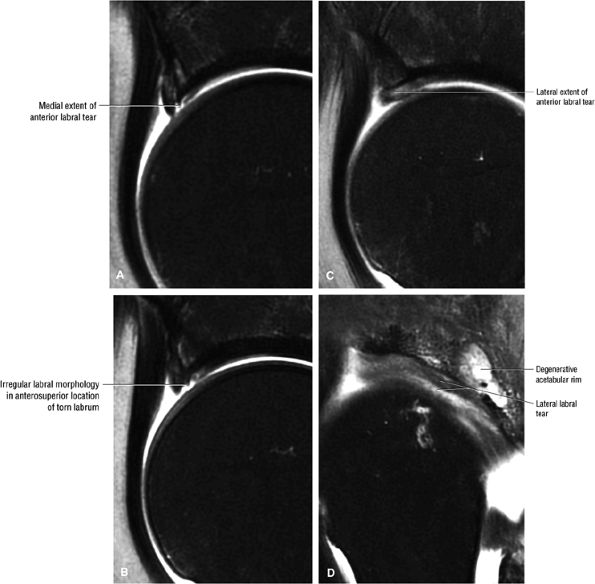

|

![]() |

FIGURE 3.156 ● Complete full-thickness tear of the gluteus minimus tendon. The gluteus medius is intact. (A) Coronal FS PD FSE image. (B) Sagittal FS PD FSE image. (C) Posterior coronal illustration.

FIGURE 3.157 ● Full-thickness tear with proximal retraction of the gluteus minimus. Coronal FS PD FSE image.

FIGURE 3.158 ● Prominent gluteus medius bursitis associated with partial tearing of the gluteus medius tendon and hyperintensity of the subgluteus bursa. Coronal FS PD FSE image.

FIGURE 3.159 ● Hydroxyapatite deposition adjacent to the minimus tendon. Calcific tendinosis (tendinitis) may involve the gluteus maximus, minimus, or medius attachments. (A) Coronal FS PD FSE image. (B) Coronal T2* gradient echo image.

-

In gluteus minimus and medius tendinosis the tendons may appear either thickened or attenuated. There is increased signal on FS PD FSE images. Non-fat-suppressed T2-weighted images demonstrate intermediate-signal-intensity tendinosis and no tearing.